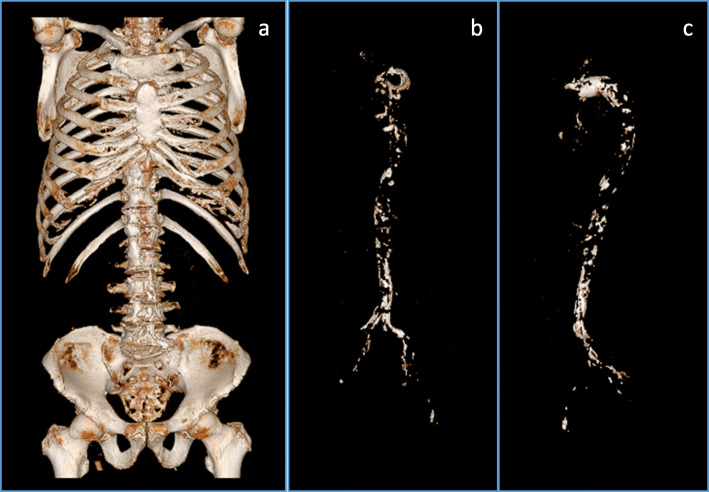

Our study subjects underwent CT scan in order to investigate the presence or absence of malignancy (91 cases), locate the source of infection (18 cases), evaluate aortic aneurysm or aortic dissection (4 cases), investigate the cause of anemia (4 cases), evaluate renal artery calcification (2 cases), and for other miscellaneous reasons (9 cases). A single CT examination often detected more than one such condition in a total of 121 patients. A representative vascular calcification image is shown in Fig. 1.

Fig. 1.

Representative image of vascular calcification using 3D imaging software. 3D images from an original CT image were reconstructed (a). After the removal of bone and the manual confirmation, the vascular calcification image is shown in (b). Rotation of the vascular calcification image (b) is shown in (c)

The present study mainly targeted the aorta in humans with reduced eGFR which is evident from representative image in Fig. 1, and we showed that ACEI/ARB user might be associated with vascular calcification. Our present results are consistent with a recent report by Herencia C. et al., showing the cause and effect relationship between angiotensin II inhibition and calcification in hyperphosphatemic milieu in vitro [10]. The in vitro study by Herencia C. et al. is based on the human aortic smooth muscle cells. Therefore, the in vitro study and our present study share a concept that the deterioration of human aortic calcification by blocking angiotensin II pathway both in clinical and in vitro point of view. In terms of vascular calcification and ACEI and/or ARB, Darabian S et al. reported that patients who received ACEI and/or ARB had a greater average of coronary artery calcification score [17], which is consistent with our results.